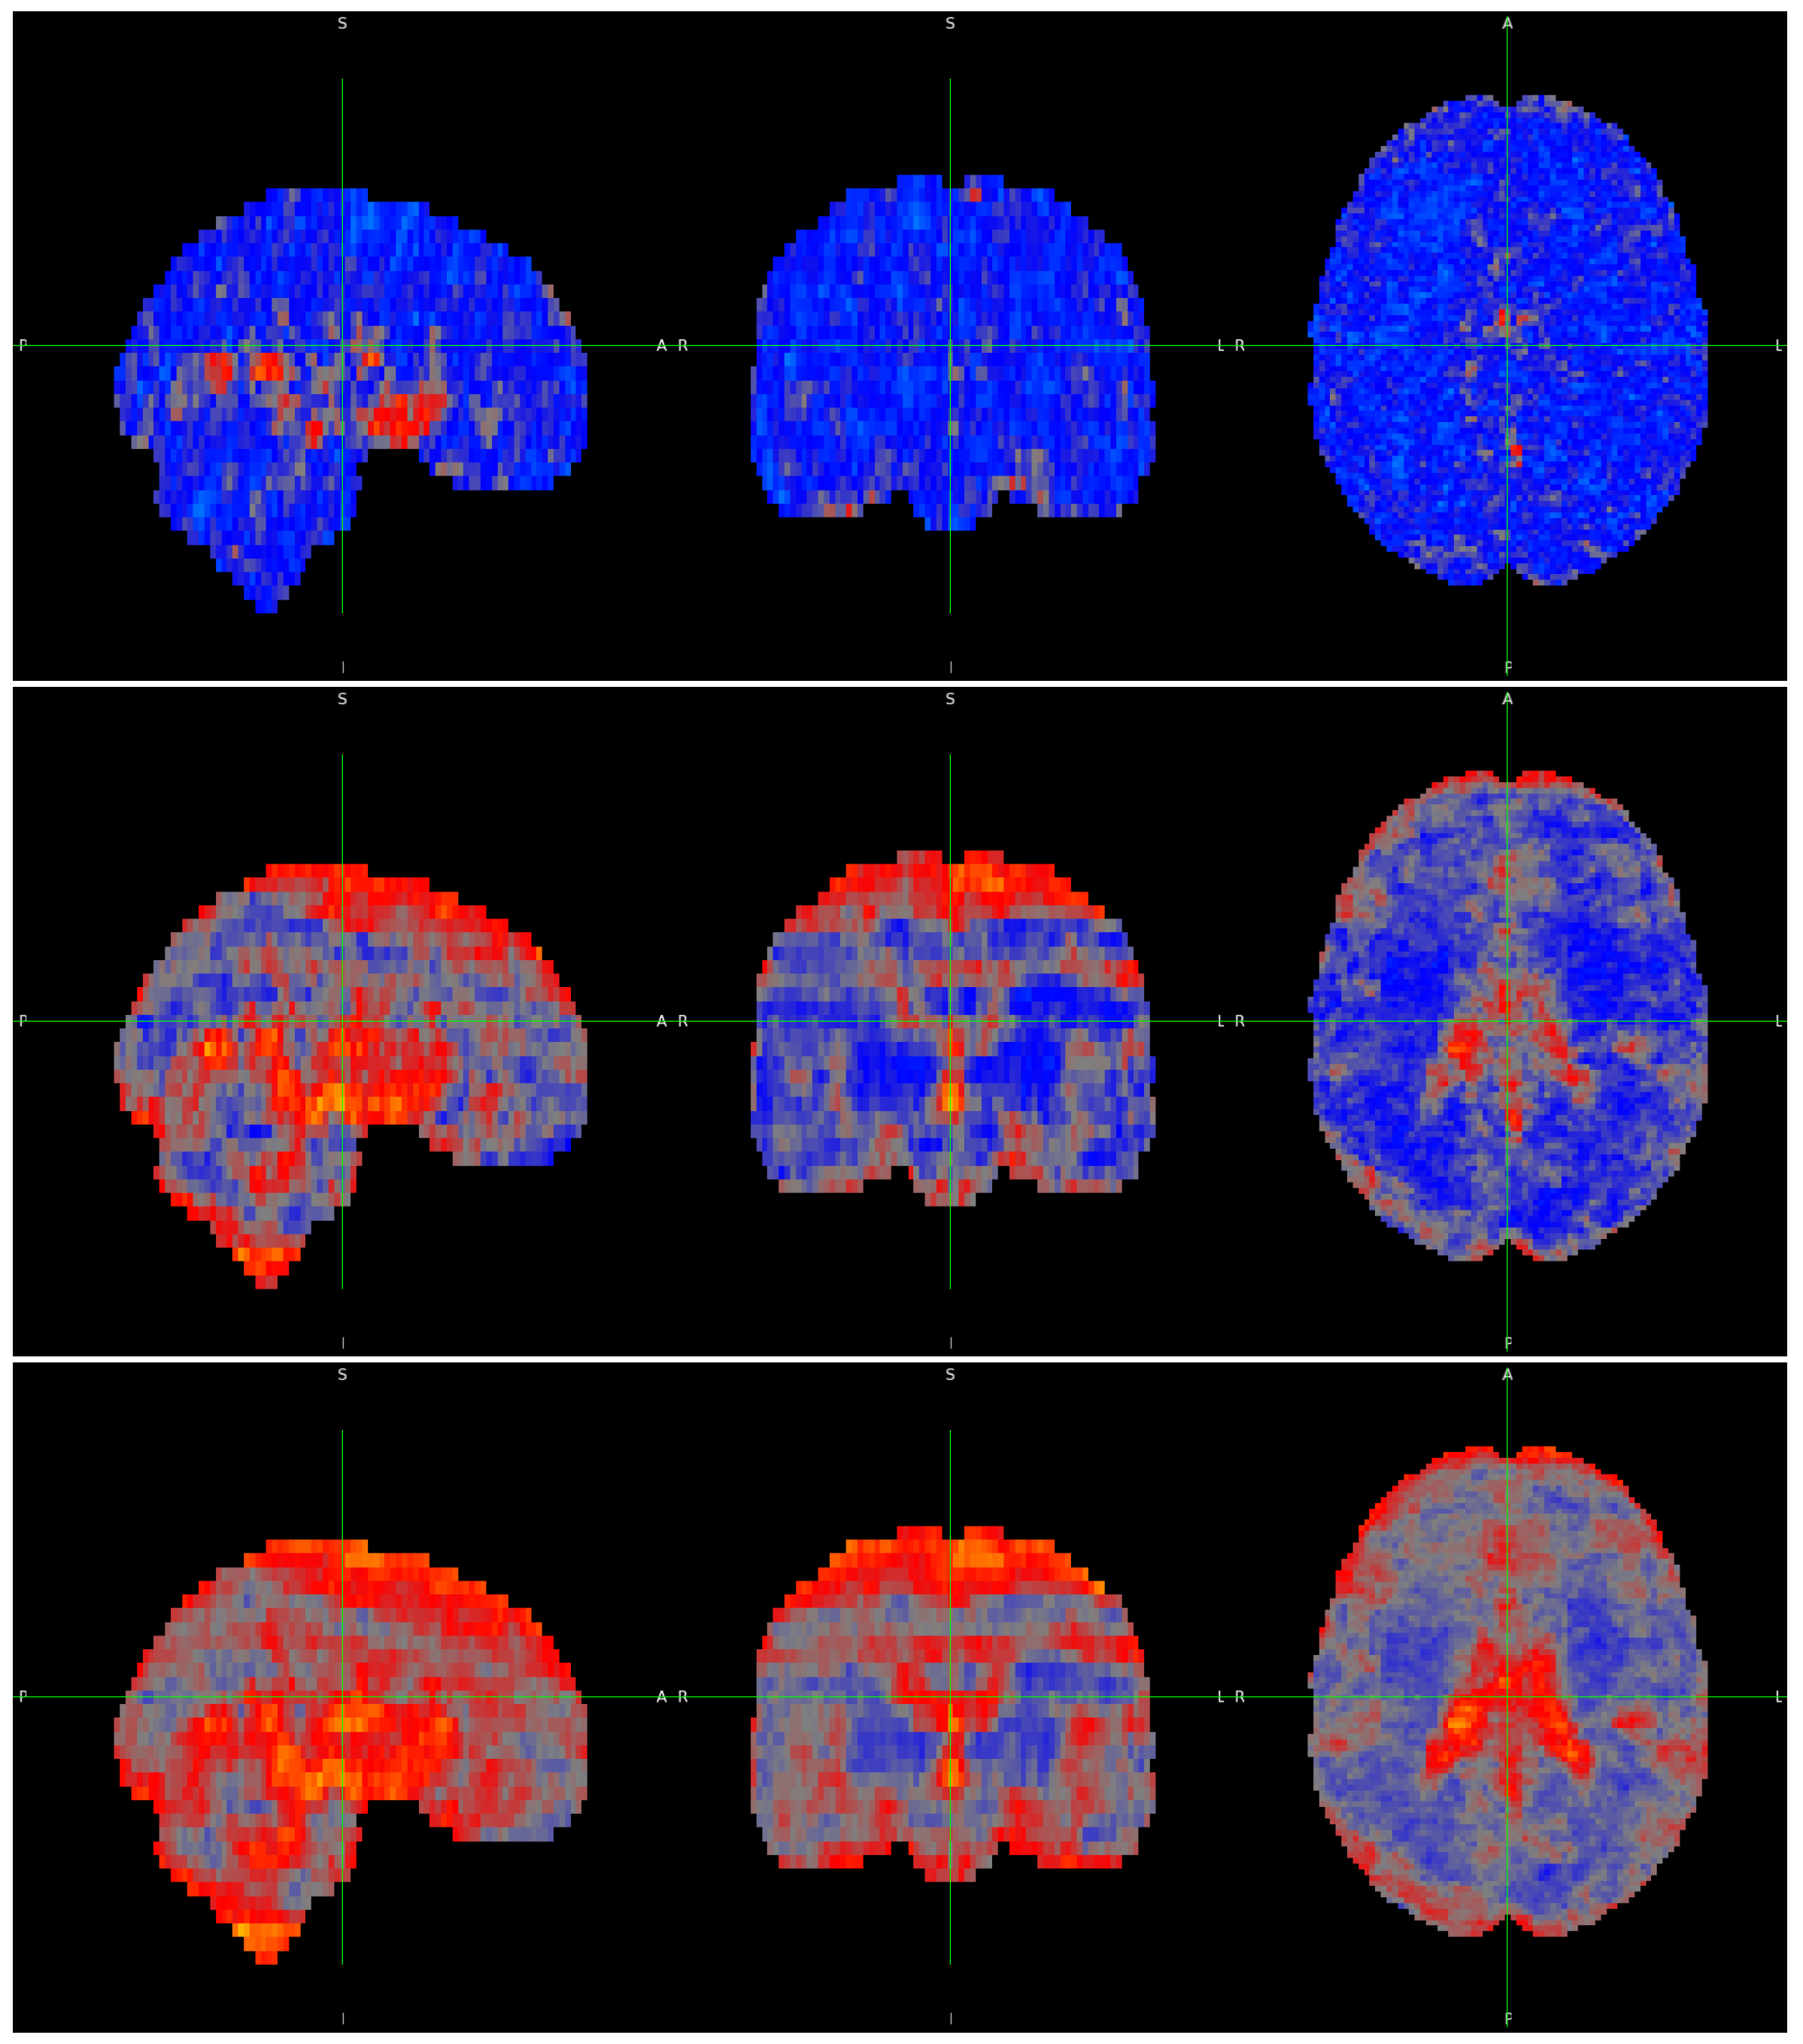

3. Results